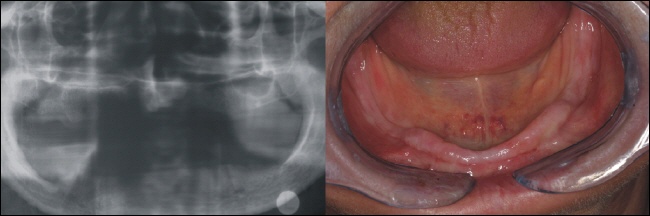

Ausgangszustand

Ein allzu typisches Problem. Die untere Prothese kann im zahnlosen Kiefer keinen Halt finden. Links sieht man das Röntgenbild und rechts die Situation im Mund.